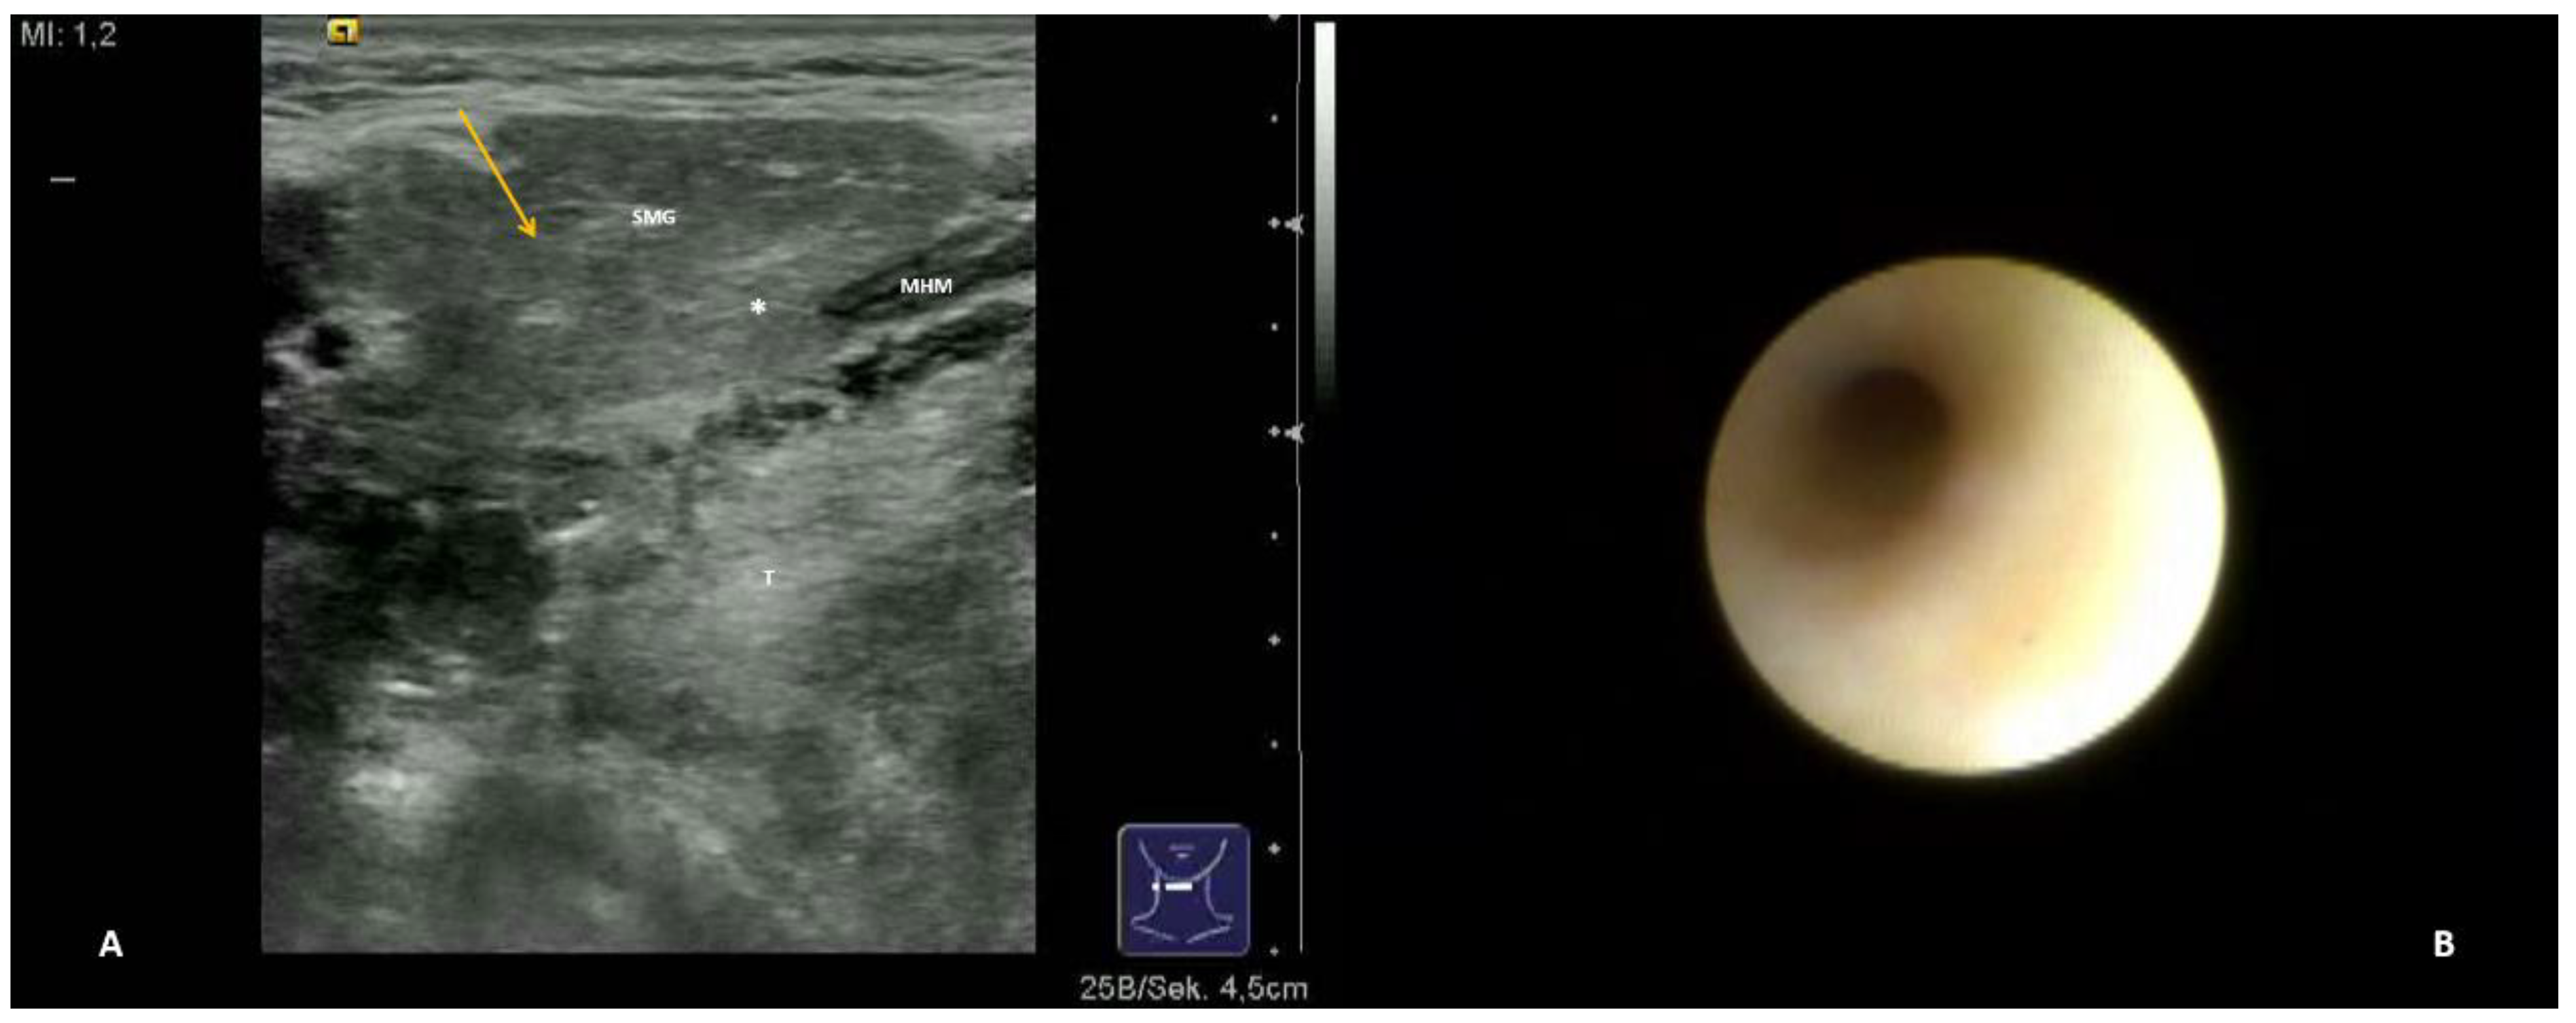

- Hypoechoic and homogeneous (no relevant loss of gland parenchyma; Figure 1A)

- Chronic sialodochitis (SD: inflammation, paleness of the duct wall, plaques, discharge; Figure 1B; Supplementary Video S1)